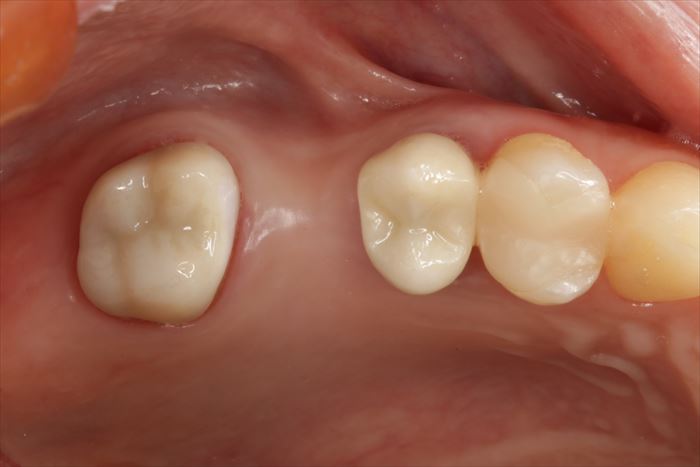

右上第一大臼歯(右上6)部分にインプラントの埋入を計画します。